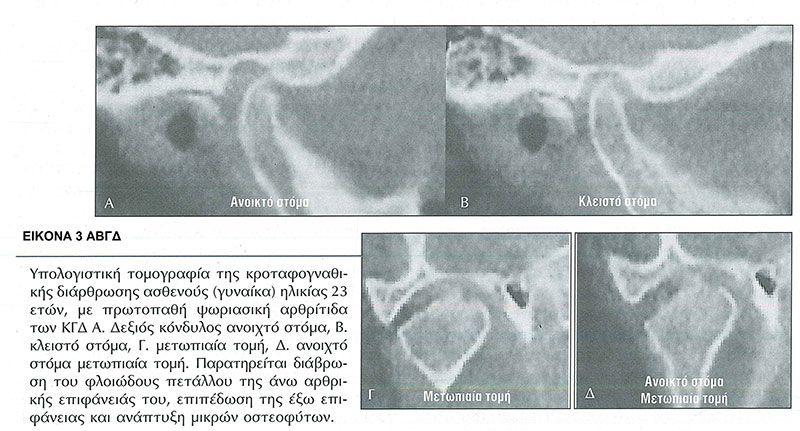

Η συνύπαρξη της ΨΑ με την ΡΑ ή της ΨΑ με την ΑΣ ή της ΨΑ και της ΟΑ είναι οι συνηθέστερες περιπτώσεις εμφάνισης των νόσων αυτών. (Εικ.3 Α, Β, Γ, Δ)

ΨΑ και ΣΣ

Τα ποσοστά προσβολής των ΚΓΔ από ΨΑ κυμαίνονται από 24 έως 82%.

Τα κλινικά σημεία και συμπτώματα από το ΣΣ εμφανίζουν οι μισοί από τους ασθενείς με ΨΑ. (7, 8)